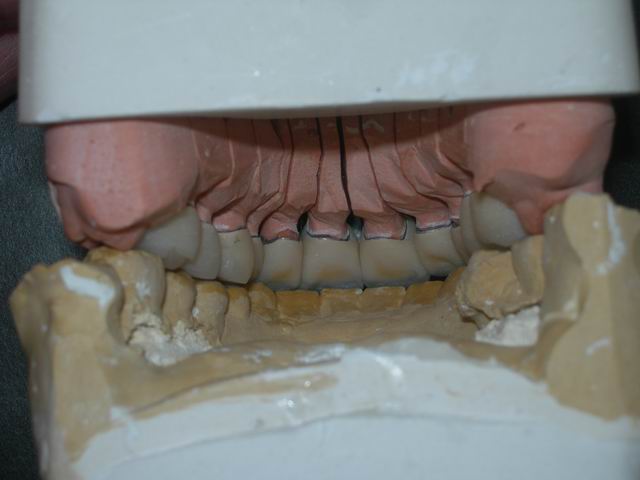

Conferência da articulação cerâmica sobre modelos: de troquéis e antagonista